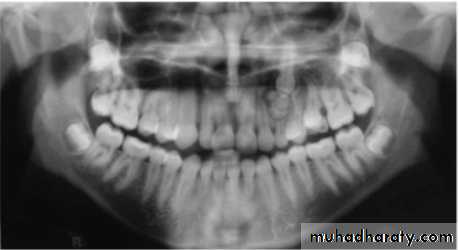

A- Supernumerary teeth (extra teeth)The presence of extra tooth obviously has great potential to disrupt normal occlusal development. Early intervention and to remove it is usually required to obtain reasonable alignment and occlusal

relationships.

Most common supernumerary teeth are:

mesiodensSuplemental lateral incisors

extra premolars

paramolar

fourth molars

multiple supernumerary teeth are found in cleidocranial dysplasiaComplications associated with supernumerary teeth are

1- Crowding2-Midline diastema

3-Displacement or rotation of of neighboring tooth

4- Root resorption

5- Prevention of eruption of adjacent teeth

2-Presence of supernumerary

teeth or deciduous root

12-TOOTH IMPACTION: Excluding third molars, commonly impacted teeth include:

Maxillary canines Maxillary central incisors